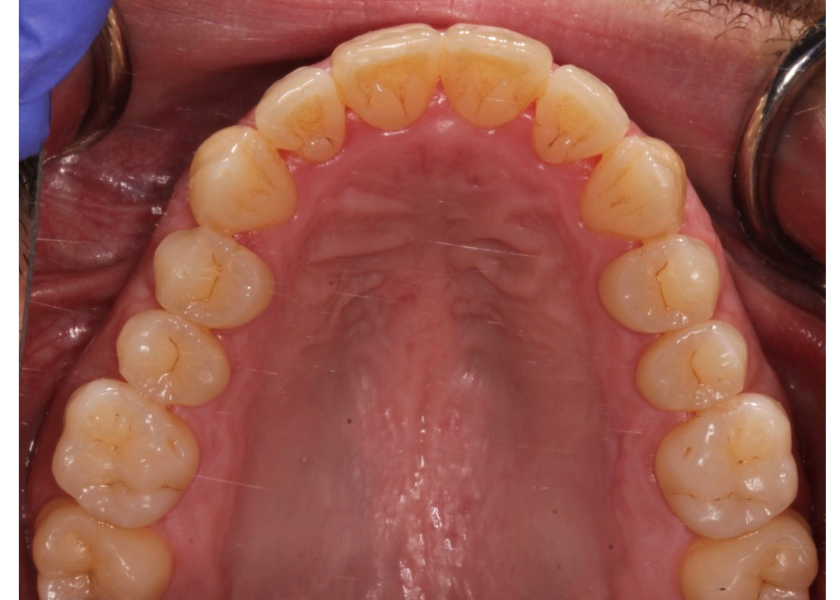

Este paciente acudió a Clínica Dental Urumea para mejorar la estética de su sonrisa. Primero se realizó un tratamiento de ortodoncia con alineadores transparentes Invisalign, para alinear y corregir la mordida cruzada.